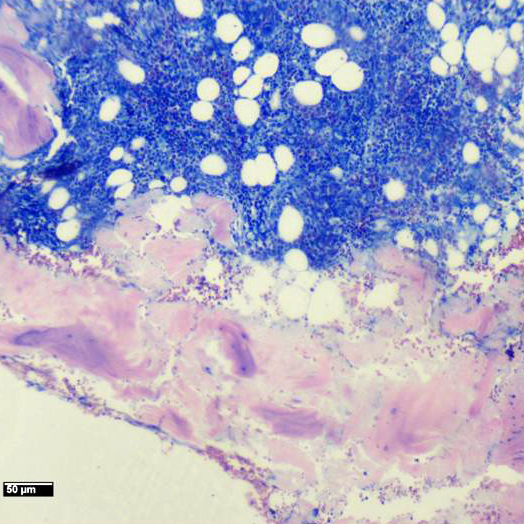

Se realiza punción de médula ósea.

Imágenes Microscopio

Histoquímica: Giemsa

MÉDULA ÓSEA HIPERCELULAR CON CAMBIOS CITOPÁTICOS COMPATIBLES CON INFECCIÓN POR PARVOVIRUS

• La morfología típica muestra una médula ósea hipocelular, no como en este caso; pero las características citológicas de los eritroblastos, resaltadas en la coloración de Giemsa, que muestran macrocariosis e inclusiones nucleares; apoyadas por los hallazgos de la PCR confirman el diagnóstico.